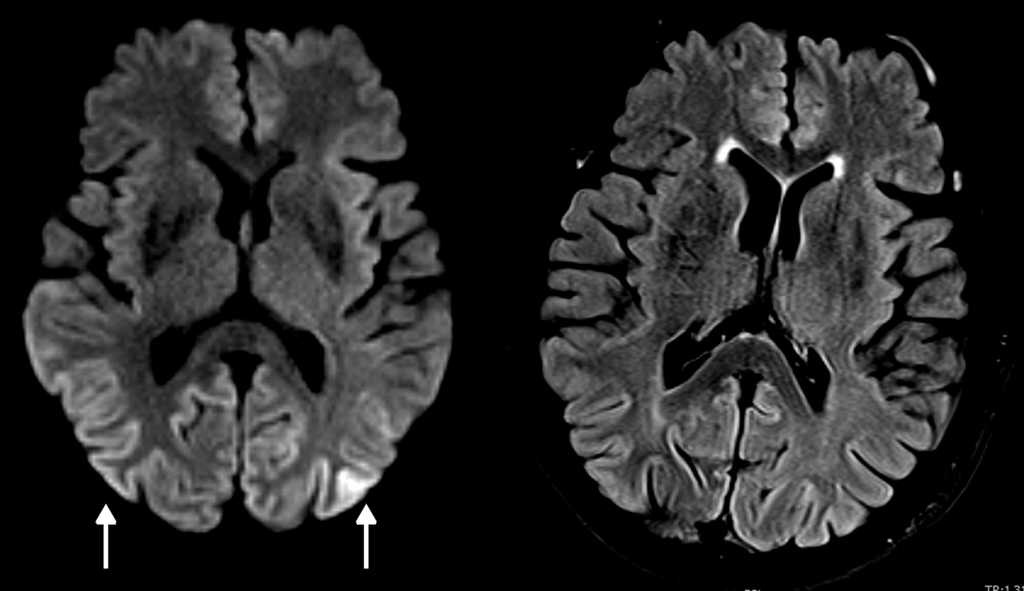

En una resonancia magnética (RM) cerebral hecha en un equipo de 3 Teslas (3 T), que se había realizado 6 semanas antes en otro centro, se observaba restricción a la difusión en la corteza parieto-occipital bilateral. Estos hallazgos fueron confirmados y superpuestos a la RM (3 T) realizada en nuestro centro al segundo día del ingreso (fig. 1). A los dos meses se llevó a cabo una RM de control con hallazgos similares, aunque menos evidentes, al ser hecha con un campo abierto de 1 T.

Los hallazgos de la RM puede ser uni o bilaterales y simétricos o asimétricos, e incluyen hiperintensidad en ponderación T2 y en atenuación del fluido en inversión-recuperación (FLAIR) de los ganglios basales (putamen y caudado), tálamo (signo del palo de hockey), corteza (manifestación temprana más común) o sustancia blanca4,5,7,8. En la ECJv los cambios se observan típicamente en el tálamo (signo del pulvinar). En la secuencia de difusión (DWI) es característica la difusión restringida persistente, especialmente evidente en los equipos de alto campo, siendo esta la secuencia más sensible para las alteraciones corticales, además de ser superior a las secuencias ponderadas en T2 y FLAIR en estadios tempranos2,7 (fig. 2). En la variante de Heidenhain son características las alteraciones de señal de los ganglios basales y típicamente del cortex occipital2,3. También se produce atrofia cerebral progresiva rápida.